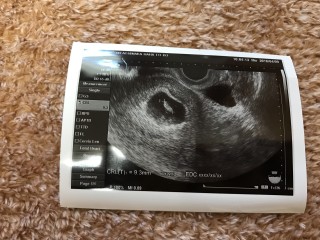

3歳差で二人目の妊娠です。

2回目でもこの時期はドキドキですね。

赤ちゃんは11.7ミリで心拍も確認できました♪

先生からも立派!と言われ一安心。これからもすくすく育ってね。